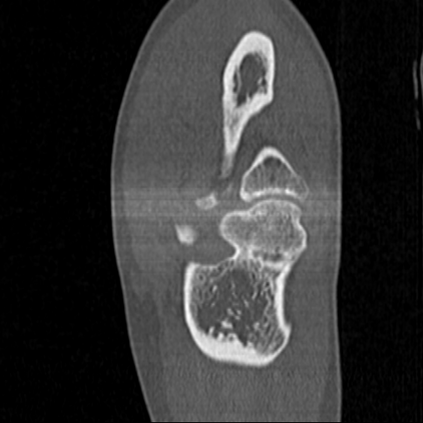

CT reconstruction provides radiologists with images for diagnosis and treatment, yet current deep learning methods are typically limited to specific anatomies and datasets, hindering generalization ability to unseen anatomies and lesions. To address this, we introduce the Multi-Organ medical image REconstruction (MORE) dataset, comprising CT scans across 9 diverse anatomies with 15 lesion types. This dataset serves two key purposes: (1) enabling robust training of deep learning models on extensive, heterogeneous data, and (2) facilitating rigorous evaluation of model generalization for CT reconstruction. We further establish a strong baseline solution that outperforms prior approaches under these challenging conditions. Our results demonstrate that: (1) a comprehensive dataset helps improve the generalization capability of models, and (2) optimization-based methods offer enhanced robustness for unseen anatomies. The MORE dataset is freely accessible under CC-BY-NC 4.0 at our project page https://more-med.github.io/